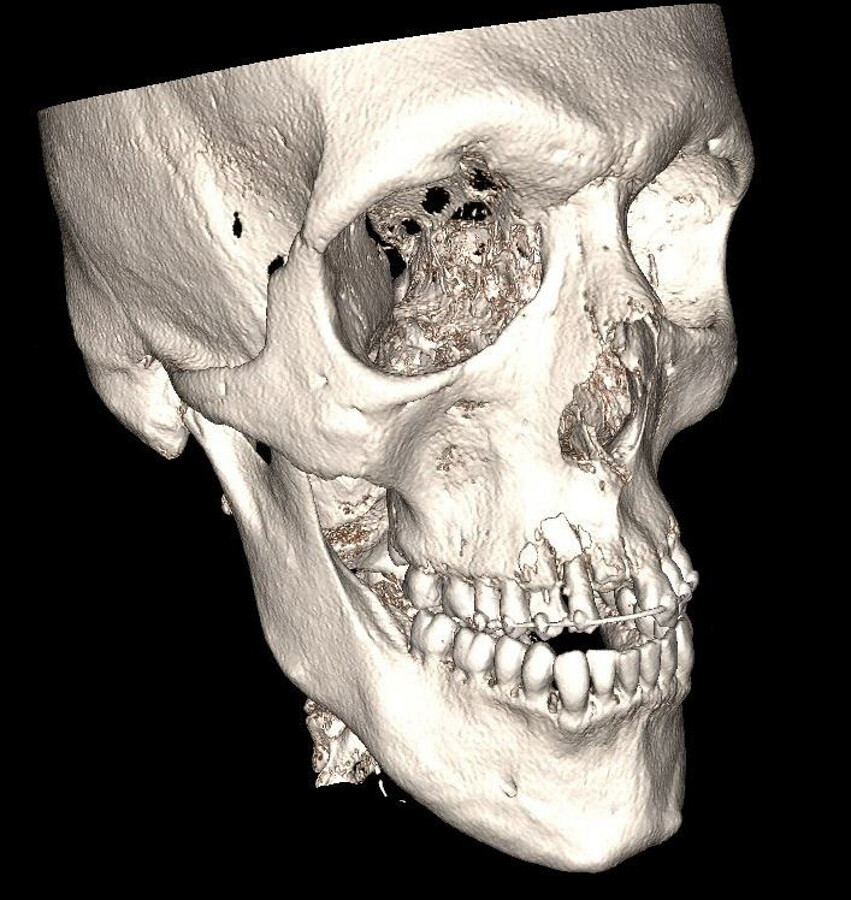

Tandfilm van de situatie kort na het ongeval. De 12 is gereponeerd en gespalkt. De kroon van de afgebroken 11 is om esthetische redenen aan de spalk gefixeerd. Tevens is de radixfractuur van de 13 zichtbaar

Na plaatsing van een spalk wordt hij naar huis gestuurd en bij de eerstvolgende afspraak komt hij bij dokter Van Minnen terecht. Vanaf dat moment hebben ze vrijwel elke maand een afspraak. Van Minnen vertelt dat de elementen 21 tot en met 13 waren aangedaan. Bij de 21 gaat het om een glazuurafwijking, de 11 en 13 zijn ernstig beschadigd en de 12 ligt er volledig uit. Deze laatste is direct na het ongeluk teruggezet en gespalkt. De wortels van de 11 en 13 zitten er dan nog wel in, maar de prognose van deze afgebroken elementen is vrij slecht. Van Minnen: “Deze wortels hebben we verwijderd en een maand na het letsel hebben we de tandkassen opgevuld met bot om de processus alveolaris zo goed mogelijk te behouden. In maart plaatsten we vervolgens de implantaten en die zijn inmiddels goed vastgegroeid. Als laatste stap van de behandeling komen eind augustus de kronen hierop.”